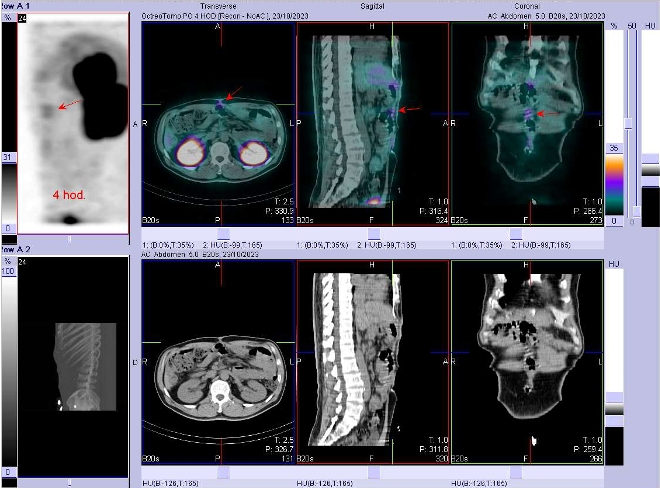

/ Obr. č. 2: Fúze SPECT/CT břicha a pánve 4 hod. po aplikaci OctreoScanu. Zaměřeno na ložisko v pravém jaterním laloku.

Popis: patologické ložisko se zvýšenou hustotou somatostatinových receptorů v dorzální části pravého jaterního laloku. Mírná akumulace radioaktivity ve střední čáře na povrchu břicha, nejspíše v jizvě po operaci. Jinde patol. ložiska nejsou patrná. Jinak fyziologická depozice radioindikátoru ve slezině, játrech, ledvinách, močovém měchýři, střevech. Nález svědčí pro jaterní metastázu neuroendokrinního nádoru pankreatu.

Prokázali jsme jaterní metastázu neuroendokrinního tumoru hlavy pankreatu.